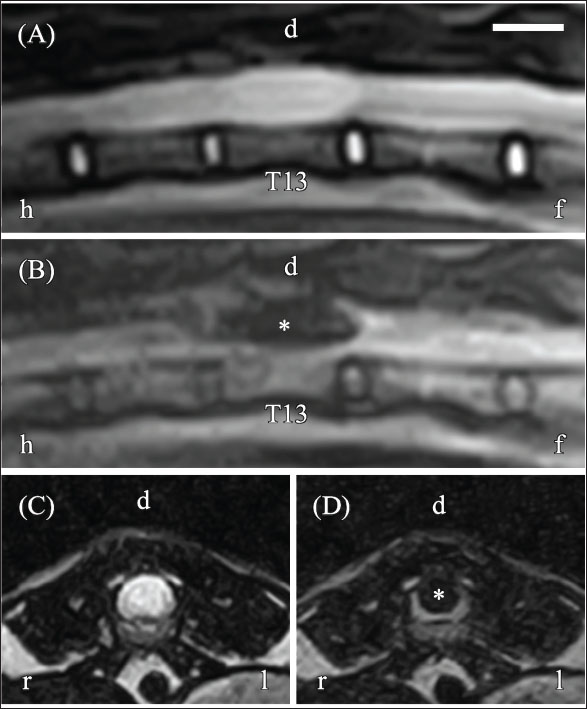

Thoracic and abdominal radiographs revealed no abnormalities. MRI was performed using an AIRIS Vento 0.3-T scanner with a knee coil (Fujifilm, Tokyo, Japan) under general anesthesia. Sequences acquired included the following: T2-weighted sagittal and transverse sequences [repetition time (TR), 3000 ms; echo time (TE), 120 ms; slice thickness, 2.5 mm; gap, 0 mm; field of view (FOV), 300 mm; matrix, 256 × 256; number of excitations (NEX), 8]; T1-weighted sagittal and transverse sequences (TR, 300 ms; TE, 15 ms; slice thickness, 2.5 mm; gap, 0 mm; FOV, 300 mm; matrix, 256 × 256; NEX, 5); pre- and post-gadolinium (Omniscan; GE Healthcare) (dose, 0.1 mmol/kg; delay after injection, approximately 1 minute); and fluid-attenuated inversion recovery (FLAIR) sagittal and transverse sequences (TR, 9,000 ms; TE, 100 ms; slice thickness, 2.5 mm; gap, 0 mm; FOV, 300 mm; matrix, 256 × 256; NEX, 2). The total imaging time was 100 min. MRI revealed a lesion on the dorsal aspect of the T13 spinal cord that appeared hyperintense on T2-weighted images (T2WI) (Fig. 2A and C) and hypointense on both T1-weighted and FLAIR images (Fig. 2B and D). The lesion measured 6.0 mm × 5.0 mm × 18.3 mm and showed no enhancement following gadolinium intravenous administration. These findings indicated a fluid-filled lesion; however, it was not possible to determine whether the lesion was intramedullary or intradural–extramedullary.

Fig. 2. Magnetic resonance imaging (MRI) of the thoracolumbar spinal cord on day 1. (A) Sagittal T2-weighted imaging (T2WI) reveals hyperintensity within the spinal cord. (B) Sagittal fluid-attenuated inversion recovery (FLAIR) imaging displays hypointensity at the same site (asterisk). (C) Transverse T2WI at the T13 level reveals hyperintensity involving nearly the entire spinal cord. (D) Transverse FLAIR imaging at the T13 level shows hypointensity in the same region, consistent with a fluid-filled lesion. However, it was not possible to determine whether the lesion was intramedullary or intradural-extramedullary because its signal characteristics were indistinguishable from the subarachnoid space. Orientation markers: h=head, f=foot, r=right, l=left. Scale bar=1 cm.

On day 91, follow-up neurological examination revealed no change in gait or postural responses of the pelvic limbs; however, superficial pain sensation had returned, and lumbar tenderness was no longer present. The MFS of the cat remained at grade 4. MRI showed hyperintensity of the T13 spinal cord on T2WI and a slit-shaped signal void on FLAIR imaging. By day 188, the cat demonstrated improved mobility, including the ability to walk with mild ataxia and jump onto a table. Neurological examination revealed loss of postural responses, and the MFS remained at grade 4. MRI findings were unchanged, showing mild hyperintensity on T2WI and a slit-shaped hypointensity on FLAIR imaging (Fig. 4A–D).

Fig. 4. MRI of the thoracolumbar spinal cord on day 188. (A) Sagittal T2WI shows hyperintensity within the spinal cord (asterisk). (B) Sagittal FLAIR imaging shows hypointensity at the corresponding site (arrow). (C) Transverse T2WI at the T13 level shows mild hyperintensity. (D) Transverse FLAIR imaging at the T13 level shows a slit-shaped hypointensity (arrow), suggesting dorsal spinal cord rupture during surgery. Orientation markers: h=head, f=foot, r=right, l=left. Scale bar=1 cm.